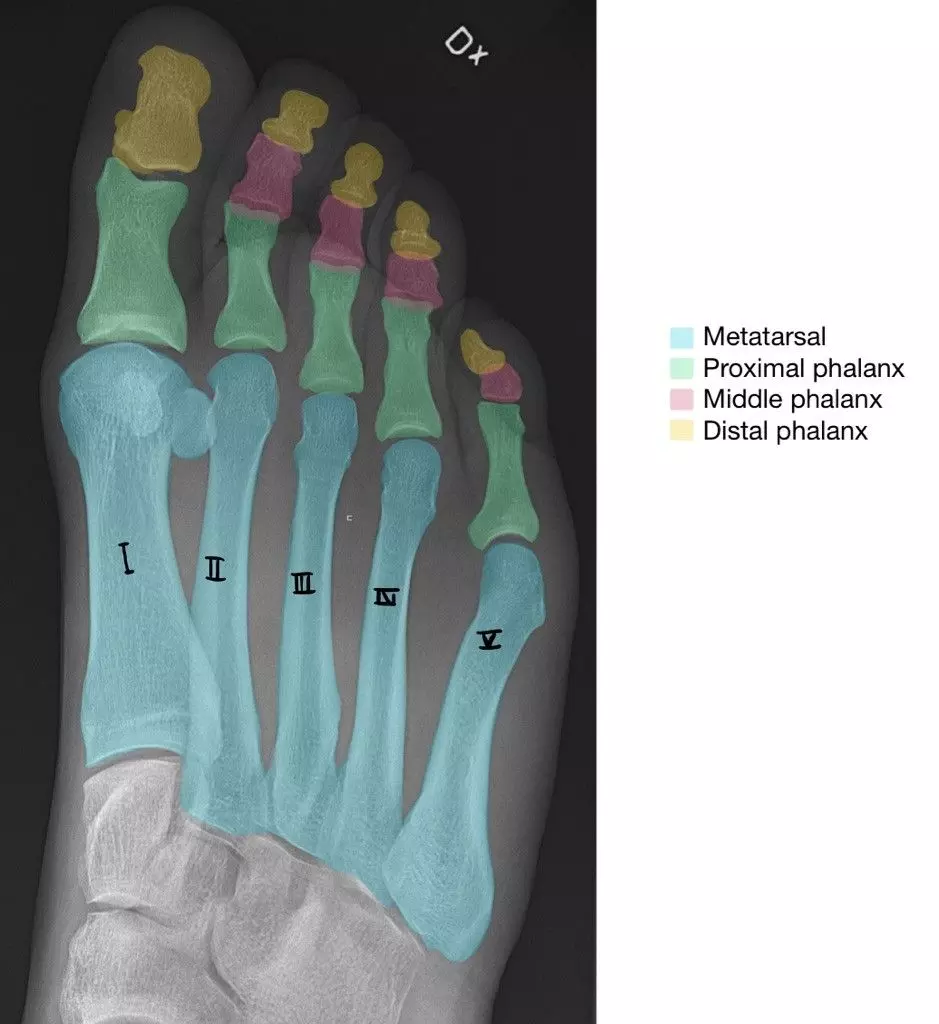

There are five metatarsals, one for each digit of the foot. They consist of a head, shaft and base, similar to the metacarpals in the hand. The base articulates with the tarsal bones to form tarsometatarsal joints. The head articulates with the phalanges of each digit via the metatarsophalangeal joint.

These are bones found within each toe. Each digit has three phalanges (proximal, middle and distal) with exception for the big toe (the hallux), which only has two (proximal and distal). The proximal phalanges articulate with the metatarsal via the metatarsophalangeal joints. Phalanges within the same digit articulate via interphalangeal joints.

Diagram - An X-Ray of the right foot. Note how the metatarsals are numbered I - V (medial to lateral)

Creative commons source by Mikael Häggström, M.D., edited by Dr. Sachin Sudhakaran [CC BY-SA 4.0 (https://creativecommons.org/licenses/by-sa/4.0)]